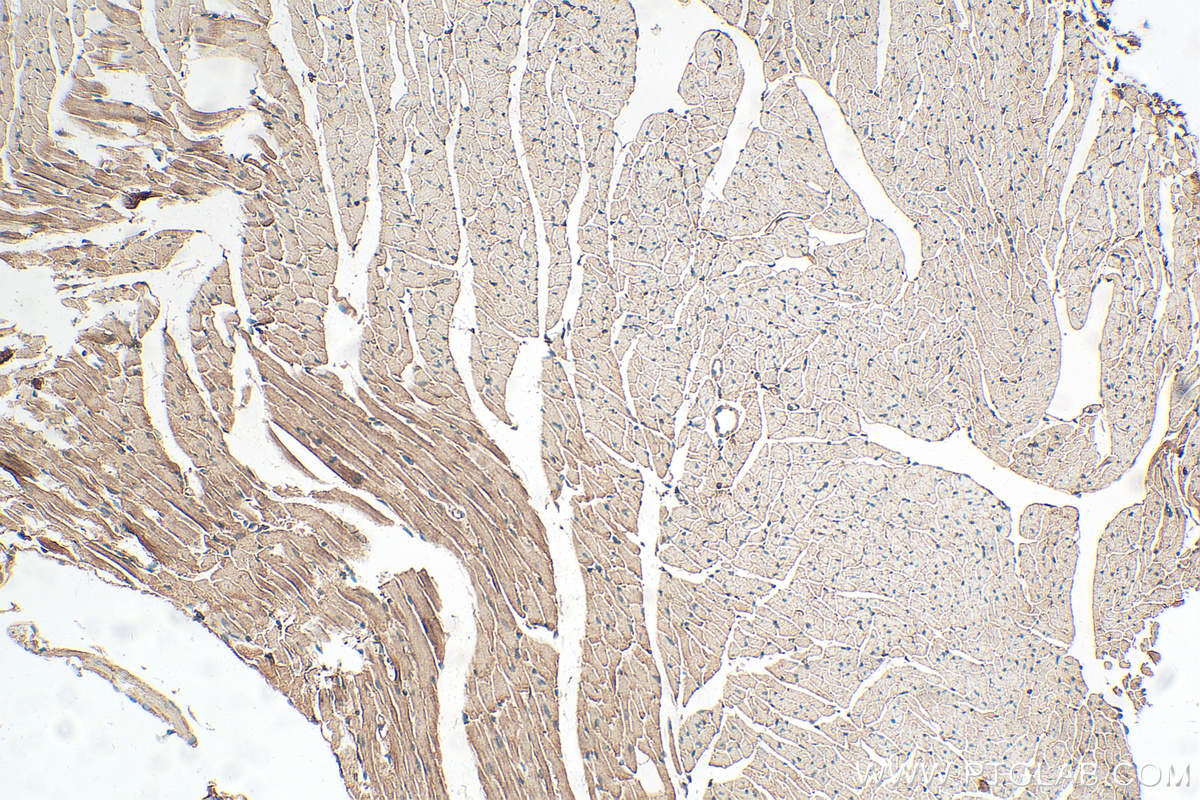

| Positive IHC detected in | mouse heart tissue, mouse skeletal muscle tissue Note: suggested antigen retrieval with TE buffer pH 9.0; (*) Alternatively, antigen retrieval may be performed with citrate buffer pH 6.0 |

14221-1-AP targets ACTN2 in WB, IHC, IF/ICC, IF-P, IF-Fro, IP, ELISA applications and shows reactivity with human, mouse, rat samples.

Alpha actinin 2 (ACTN2) belongs to the alpha-actinin family and is expressed in both skeletal and cardiac muscles and functions to anchor myofibrillar actin thin filaments and titin to Z-discs (PMID: 30701273). ACTN2 is an actin-binding protein with multiple roles in different cell types. In nonmuscle cells, the cytoskeletal isoform is found along microfilament bundles and adherens-type junctions, where it is involved in binding actin to the membrane. In contrast, skeletal, cardiac, and smooth muscle isoforms are localized to the Z disc and analogous dense bodies, where they help anchor the myofibrillar actin filaments. Mutations in ACTN2 are associated with hypertrophic cardiomyopathy, as well as dilated cardiomyopathy and endocardial fibroelastosis (PMID: 20022194, 14567970).